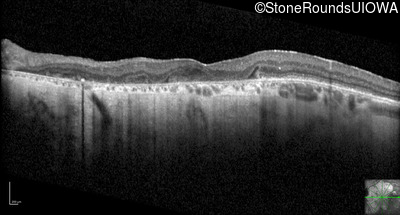

Optical Coherence Tomography - Left - 20/200

Exemplar / OCT Stack